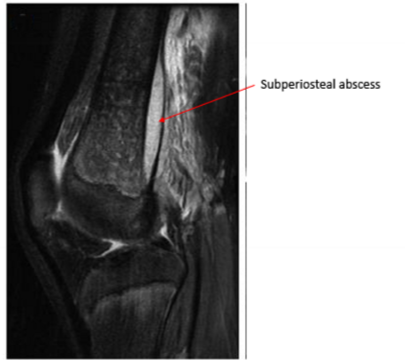

Identify